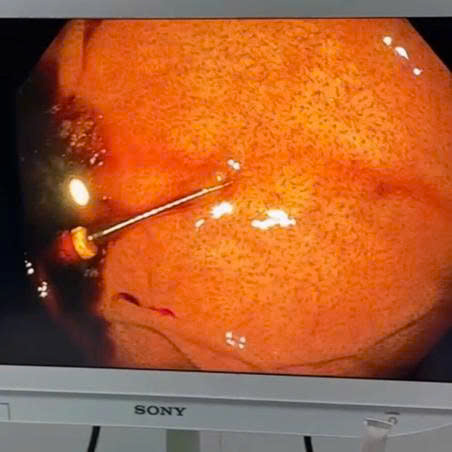

Vừa qua, Bệnh viện Đa khoa Tân Yên đã tiếp nhận và xử trí thành công một trường hợp bệnh nhân nuốt phải dụng cụ làm răng rơi xuống dạ dày.

Sau khi thăm khám lâm sàng, khai thác bệnh sử và thực hiện các cận lâm sàng cần thiết, các bác sĩ xác định dị vật nằm trong dạ dày, tiềm ẩn nguy cơ gây tổn thương niêm mạc và biến chứng nếu không được xử trí kịp thời. Bệnh nhân được chỉ định nội soi can thiệp cấp cứu nhằm loại bỏ dị vật sớm, hạn chế tối đa nguy cơ tổn thương đường tiêu hóa

Nhờ hệ thống nội soi hiện đại cùng sự phối hợp chặt chẽ, chuyên nghiệp của ê-kíp bác sĩ, dị vật đã được gắp ra an toàn qua đường nội soi, không cần phẫu thuật. Thủ thuật diễn ra thuận lợi, ít xâm lấn, giảm thiểu nguy cơ biến chứng. Sau can thiệp, tình trạng bệnh nhân ổn định.